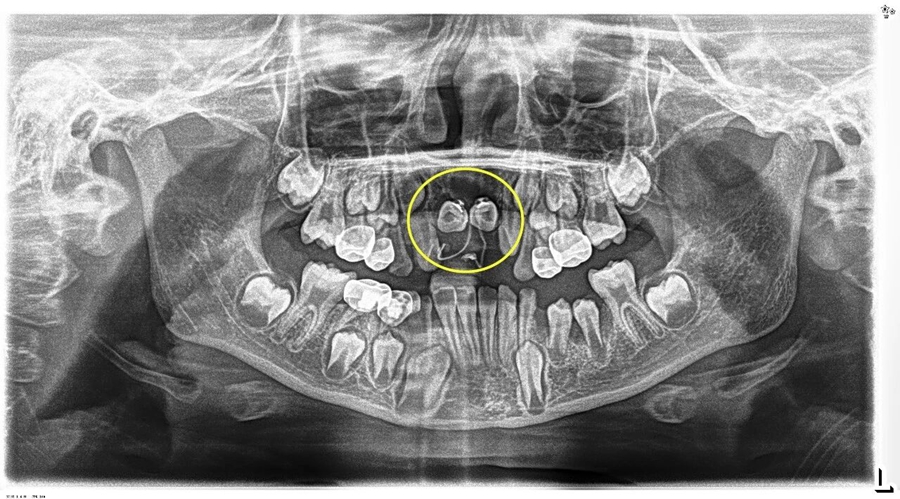

小胡已经9岁了,本该完成换牙的“新门牙”却迟迟没有萌出的迹象。家长带着他来到青岛市妇女儿童医院检查,拍摄 X 光片后发现,小胡的上颌骨内竟然埋伏着2颗多生牙,这两颗 "不速之客" 横着长在门牙牙根处,位置高至鼻底,还伴随唇向倾斜,阻碍了恒中切牙的正常萌出。

术后小胡恢复非常顺利。第一次复查时,两颗恒中切牙的舌侧扣和弹性附件的影像,下图可见: